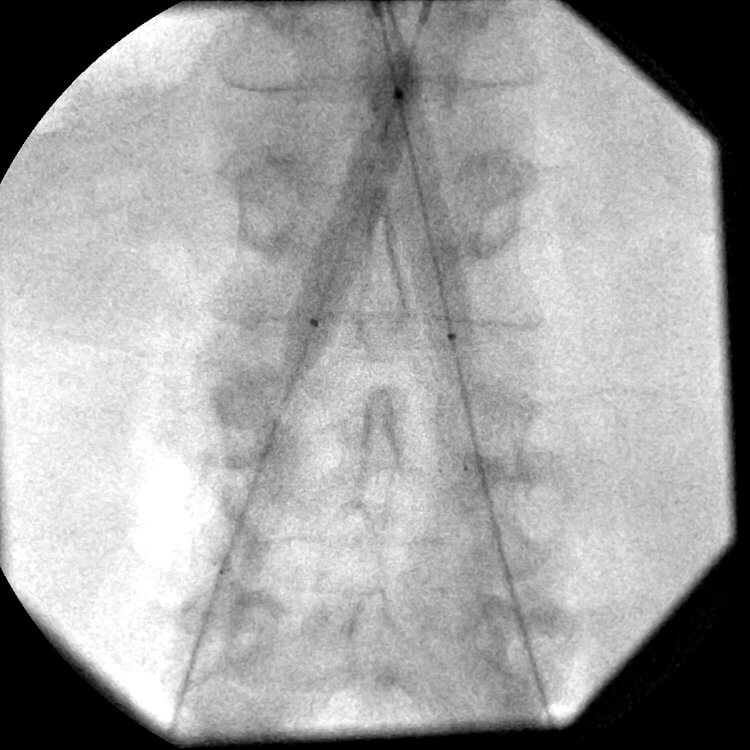

Image from an abdominal aortogram after stent placement showing restored patency in the iliac vessels bilaterally. -

Image of the lower pelvis and common femoral artery bifurcations after stent placement showing restored patency and good flow to both lower extremities.